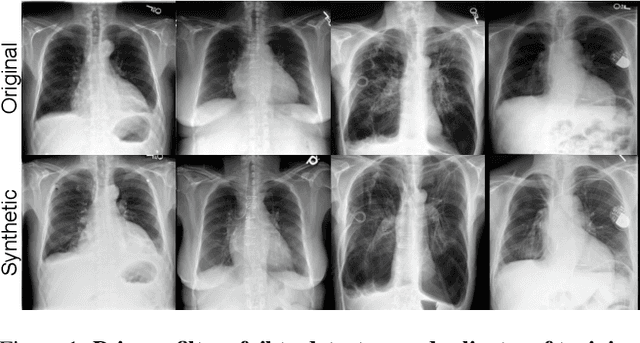

Abstract:The generation of privacy-preserving synthetic datasets is a promising avenue for overcoming data scarcity in medical AI research. Post-hoc privacy filtering techniques, designed to remove samples containing personally identifiable information, have recently been proposed as a solution. However, their effectiveness remains largely unverified. This work presents a rigorous evaluation of a filtering pipeline applied to chest X-ray synthesis. Contrary to claims from the original publications, our results demonstrate that current filters exhibit limited specificity and consistency, achieving high sensitivity only for real images while failing to reliably detect near-duplicates generated from training data. These results demonstrate a critical limitation of post-hoc filtering: rather than effectively safeguarding patient privacy, these methods may provide a false sense of security while leaving unacceptable levels of patient information exposed. We conclude that substantial advances in filter design are needed before these methods can be confidently deployed in sensitive applications.